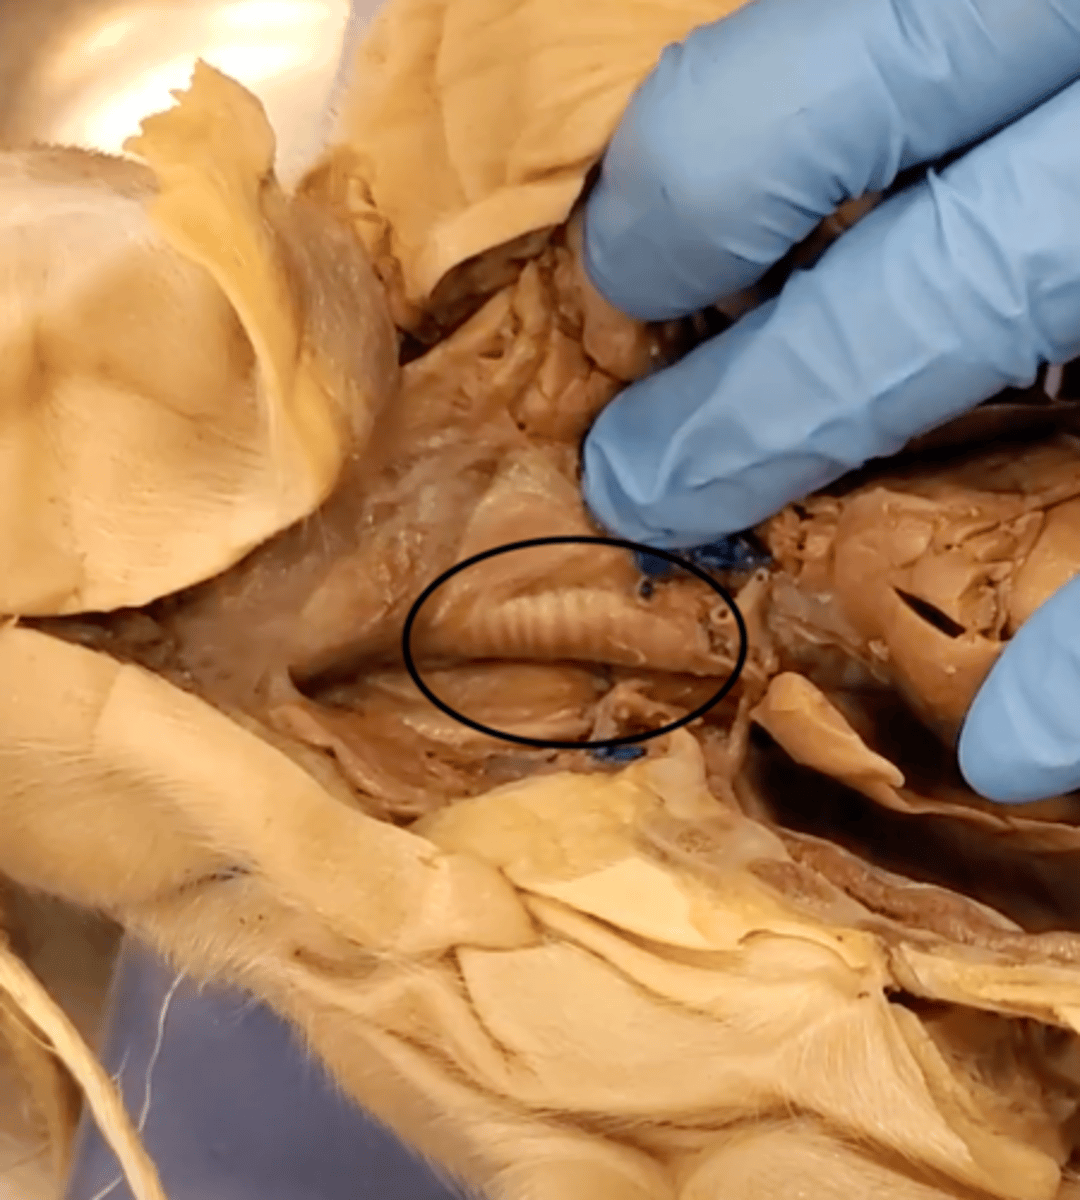

trachea

windpipe, with c-shaped cartilage ring which stiffens the windpipe for easy air passage.

lungs

Main organs of the respiratory system

heart

A hollow, muscular organ that pumps blood throughout the body.

diaphragm

Large, flat muscle at the bottom of the chest cavity that helps with breathing

esophagus

A muscular tube that connects the mouth to the stomach.